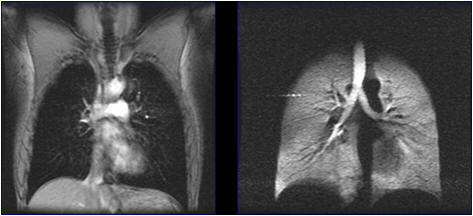

Scientists at the Sir Pete Mansfield Imaging Center have developed a new process that will give a clearer picture of lung disease using specially treated krypton gas. Once inhaled, the gas helps the spaces inside the lungs stand out in an MRI scan. This novel imaging method called “Inhaled Hyperpolarized Gas MRI,” uses lasers to “hyperpolarize” a noble gas, which then aligns the nuclei of the gas so it shows up on an MRI scan.

The team from the the University of Nottingham announced that they’ve developed a new technique to generate hyperpolarized krypton gas at high purity. A higher purity means that the gas will work even better as a contrast agent for pulmonary MRI.

This development significantly improves the potential usefulness of laser-pumped krypton-83 as MRI contrast agent for clinical applications.

Hyperpolarized krypton-83 is currently being developed for whole body MRI at high magnetic field strength in the Sir Peter Mansfield Imaging Centre’s large 7 Tesla scanner. Studies will be carried out first on healthy volunteers before progressing to patient trials at a later phase.